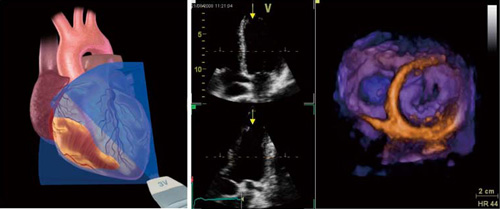

[A12295555]実践3D心エコー図法

実践3D心エコー図法【電子版】 | 医書.jp,さまざまな種類の心エコー検査「3D心エコー検査」 | VIEW Medical Gallery Site,3D心エコー:どうやって使えば手術に役立てられるか? 解剖学的評価を中心に,次世代のリアルタイム3D心エコー装置の開発-技術解説 - GEヘルスケア・ジャパン株式会社 - inNavi Suite,ACUSON SC2000」によるリアルタイムFull Volume Imagingの活用法 - 技術解説 - シーメンス・ジャパン株式会社 - inNavi Suite